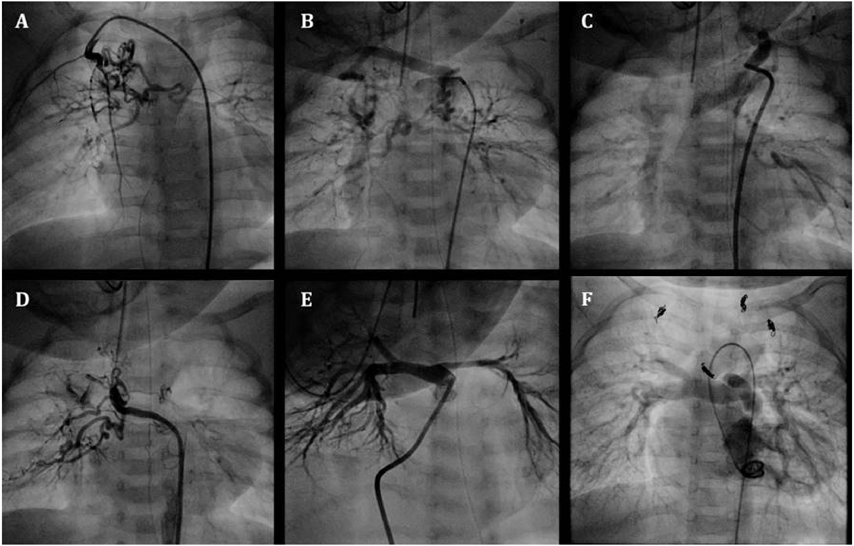

Fig. 1 Angiography of double outlet right ventricle, subarterial (doubly-committed) ventricular septal defect, and pulmonary valve stenosis with major aortopulmonary collateral arteries (MAPCAs) in a 3-month-old boy

A–E: Frontal views of the MAPCAs in selective angiography. F: Cranially angled left anterior oblique view of the native diminutive pulmonary artery (pulmonary artery index: PAI 49 mm2/m2) after the first balloon valvuoplasty. G: Final pulmonary artery (PA) angiography after transcatheter rehabilitation of the native PA at 20 months of age (PAI 135 mm2/m2)

An infant weighing 3438 g was delivered vaginally at 39 weeks’ gestation. He was diagnosed with pulmonary atresia, ventricular septal defect, and MAPCAs by fetal echocardiography. In addition, rectal-cutaneous fistula, bilateral inguinal hernias, and 22q11.2 deletion syndrome were also present. He was transferred to our hospital at 3 months of age for cyanosis and diagnosed with a double outlet right ventricle, subarterial (doubly-committed) ventricular septal defect, pulmonary valve stenosis with a 52 mmHg pressure gradient involving a diminutive tethered pulmonary valve (diameter: 3.7 mm, z score: −6.4), right aortic arch, and MAPCAs via echocardiography. His clinical condition was almost stable with 75% of oxygen saturation (SaO2) at the time of admission. The first cardiac catheterization revealed five MAPCAs originating from the subclavian artery, descending aorta, and celiac artery (Fig. 1A–E), and a diminutive native PA (PA index [PAI] 49 mm2/m2)6) (Fig. 1F). Each MAPCA had sufficient dual supply with the native PA. In other words, the native PA was connected to the entire pulmonary vascular field. The initial BVP was performed with full expansion of a 5.0 mm Tyshak II balloon (NuMED, Hopkinton, New York). Immediately after balloon deflation, the patient’s SaO2 increased to 85% and TAE of the four MAPCAs was performed in order to promote rehabilitation of the native PA. The post-interventional course was uneventful, and SaO2 was 85% at discharge from the hospital. At 7 months of age, he received a second cardiac catheterization. The native PA had grown to a PAI of 87 mm2/m2 and TAE of the minor aortopulmonary collateral arteries was performed. Because of the onset of cyanosis, a third cardiac catheterization was performed at 11 months of age. The native PA had grown to a PAI of 137 mm2/m2 and the second BVP was performed for the pulmonary valve (diameter: 6.5 mm, z score: −3.6) with full expansion of 7.0 mm and 8.0 mm Sterling balloons (Boston Scientific, Natick, MA). The patient’s SaO2 increased from 75% to 85% and TAE of the one remaining MAPCA was performed. After bilateral inguinal hernia repair surgery, a final cardiac catheterization was performed at 20 months of age. It revealed good pulmonary vascular condition with acceptable mean pulmonary artery pressure (15 mmHg), pulmonary vascular resistance (1.8 U・m2) and PAI (135 mm2/m2 :Fig. 1G). TAE of the residual minor collateral arteries was performed. During this period, pulmonary valve regurgitation remained at a mild level. At 25 months of age, he underwent a complete repair with a transannular patch. The postoperative course was uneventful, and echocardiography indicated acceptable right ventricular pressure; tricuspid regurgitation velocity was 3.1 m/s and inter-ventricular septum was round during systole in short axis view.